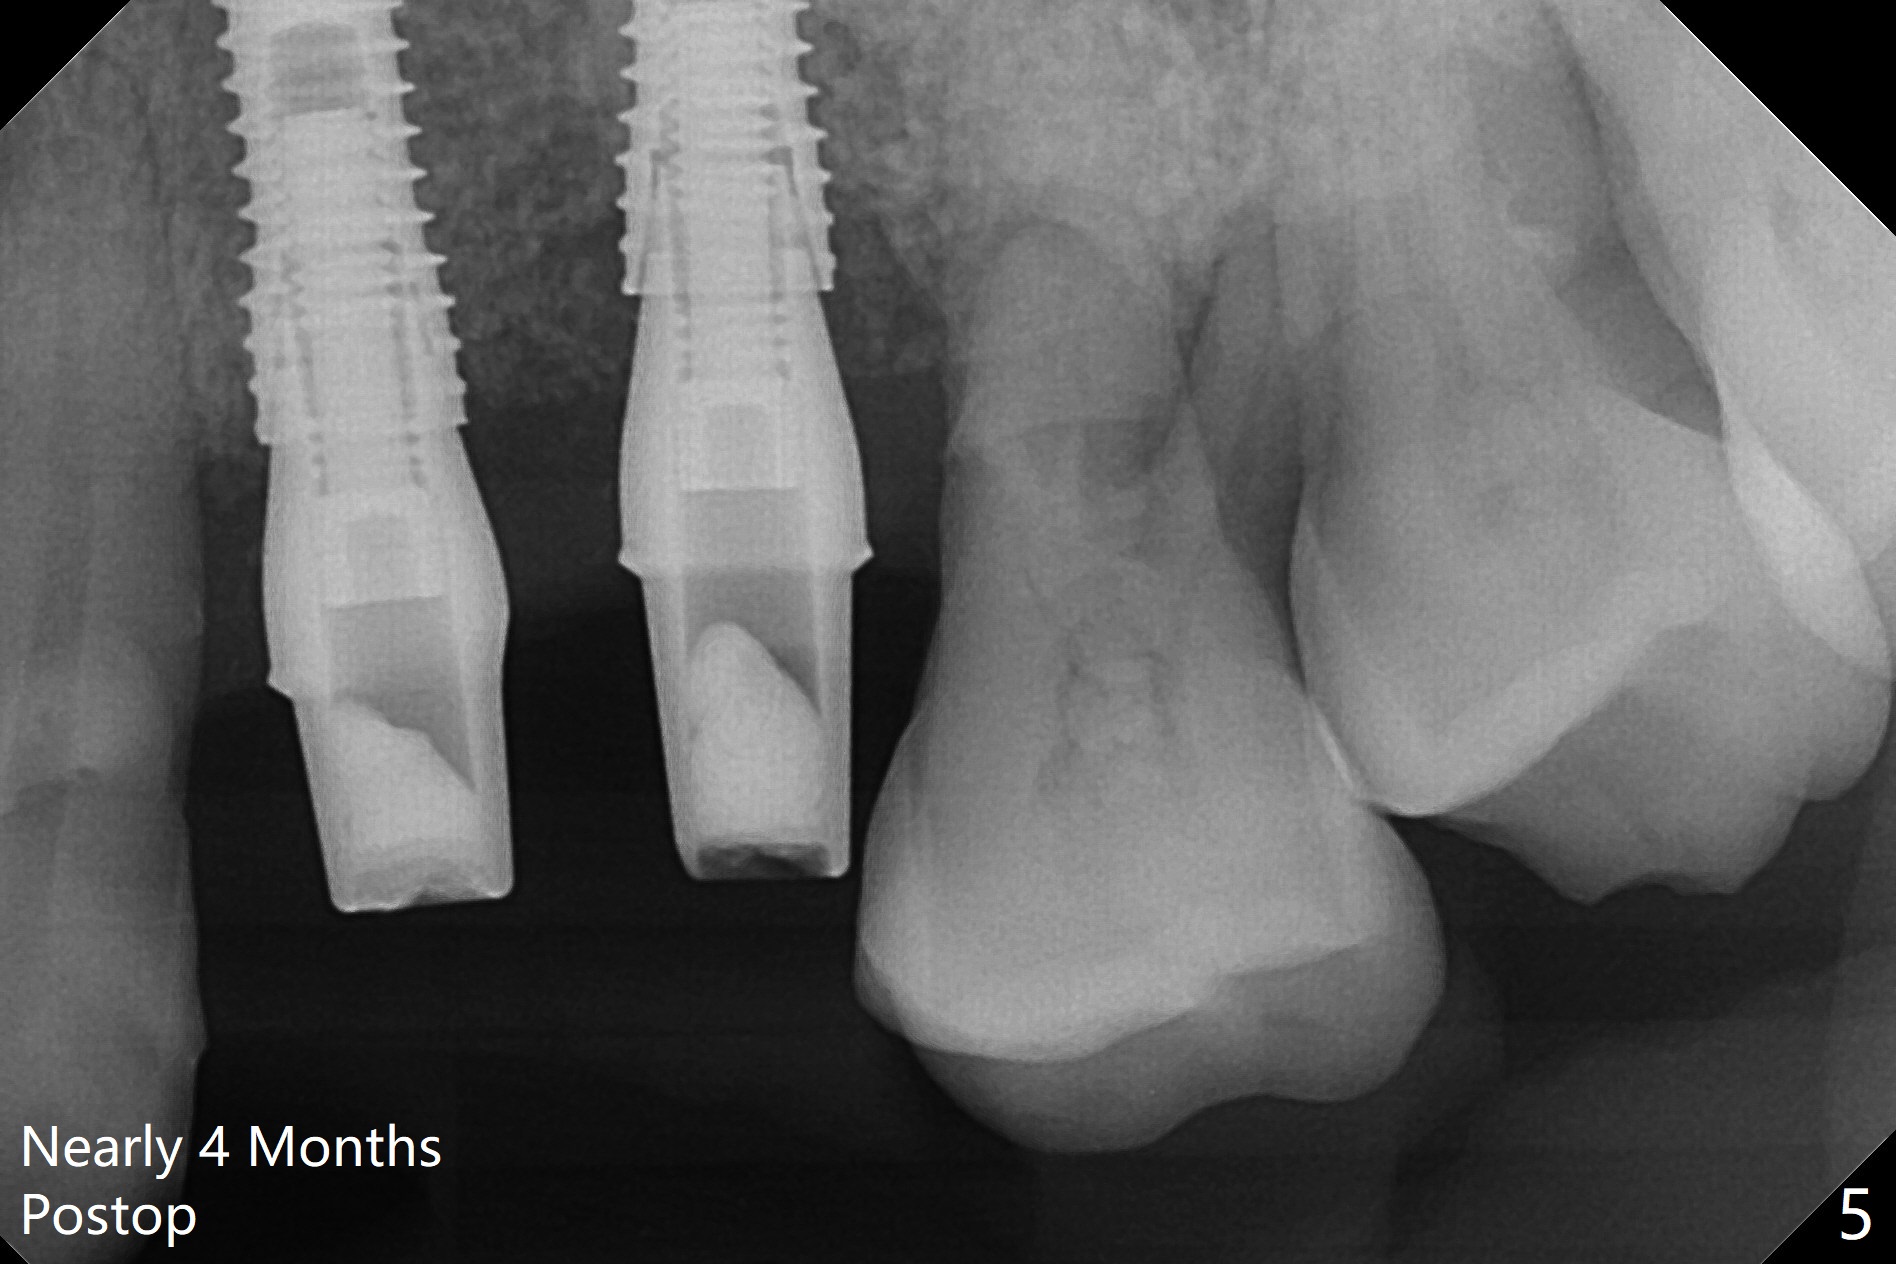

A 66-year-old woman returns to office requesting implant placement at #12 and 13 at an appointment supposed for #5 impression. Depth of osteotomy is 20 mm (gingival level, Fig.1 ( 2mm)). After correction of trajectory at #12 and 3 mm drill for 16 mm at the sites, two of 3.8x16 mm implant are placed with insertion torques of 35 and 15 Ncm, respectively (Fig.2). Before and after change into shorter abutments (4.5x4(4) and (5)), Vera Graft is placed (Fig.3 *). To increase stability, either increase the diameter (4 (Fig.4 at #5) or 4.5 mm instead of 3.8) or length of the implants (red dashed line: sinus floor). Or use dummy implants. The allograft appears to have been incorporated into the host bone nearly 4 months postop (Fig.5). The abutment of the isolate implant at #5 becomes loose twice (Fig.4). To reduce the chance of abutment loosening at #12 and 13, can you make splinted crowns? If the two separate crowns have been fabricated, can you make a slot (with light undercut) in the proximal area of each crown (Fig.6 (occlusal view): S) in addition to access hole (A)? After cementation, composite will be placed in the slots (lock) so that the crowns will not rotate and become loose.